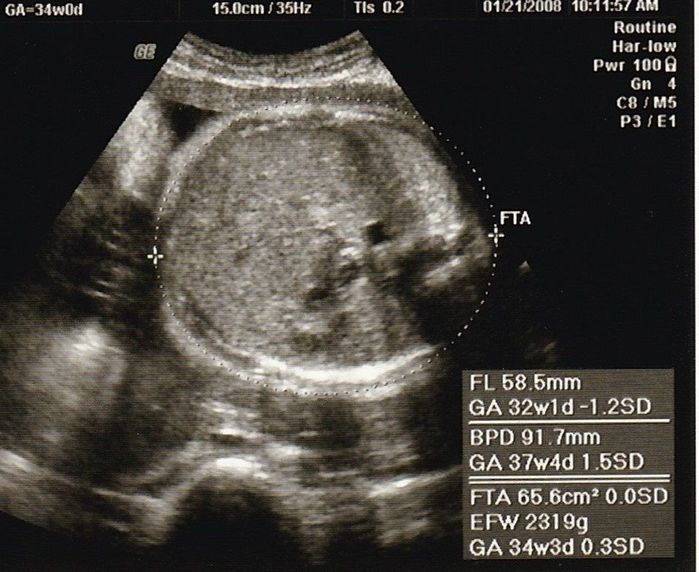

妊娠34週目のエコー写真

最後の血液検査があり、「妊娠37週を超えると正期産に入りますよ」と聞き、「妊婦生活も終わりに近づいているのだな」と感じた検診でした。「今のうちにやりたいことを」と思いましたが、結局、雑誌や本を読むくらいしかできなかったです。美容院に行けなくなるからと、私を含め、髪を切る人が多かった気がします。